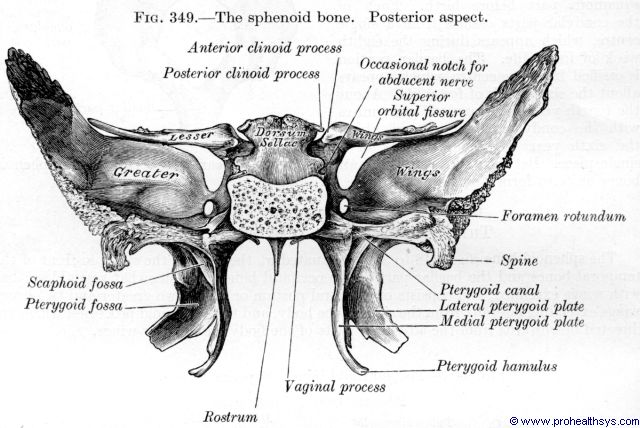

Sphenoid bone

-

pterygoid hamulus

-

Foramen rotundum

-

Foramen ovale

-

Foramen spinosum

-

Pterygoid canal

-

Foramen lacerum (破裂孔)

-

Optic canal

- CN II

- Ophthalmic a.

-

Sup. orbital fissure

- Ophthalmic n.(CN V1)/ v.

- CN III, IV, VI

相鄰骨

F, O, T, E, Pr, V, Z, Pl, Mx

上視圖

前視圖

後視圖